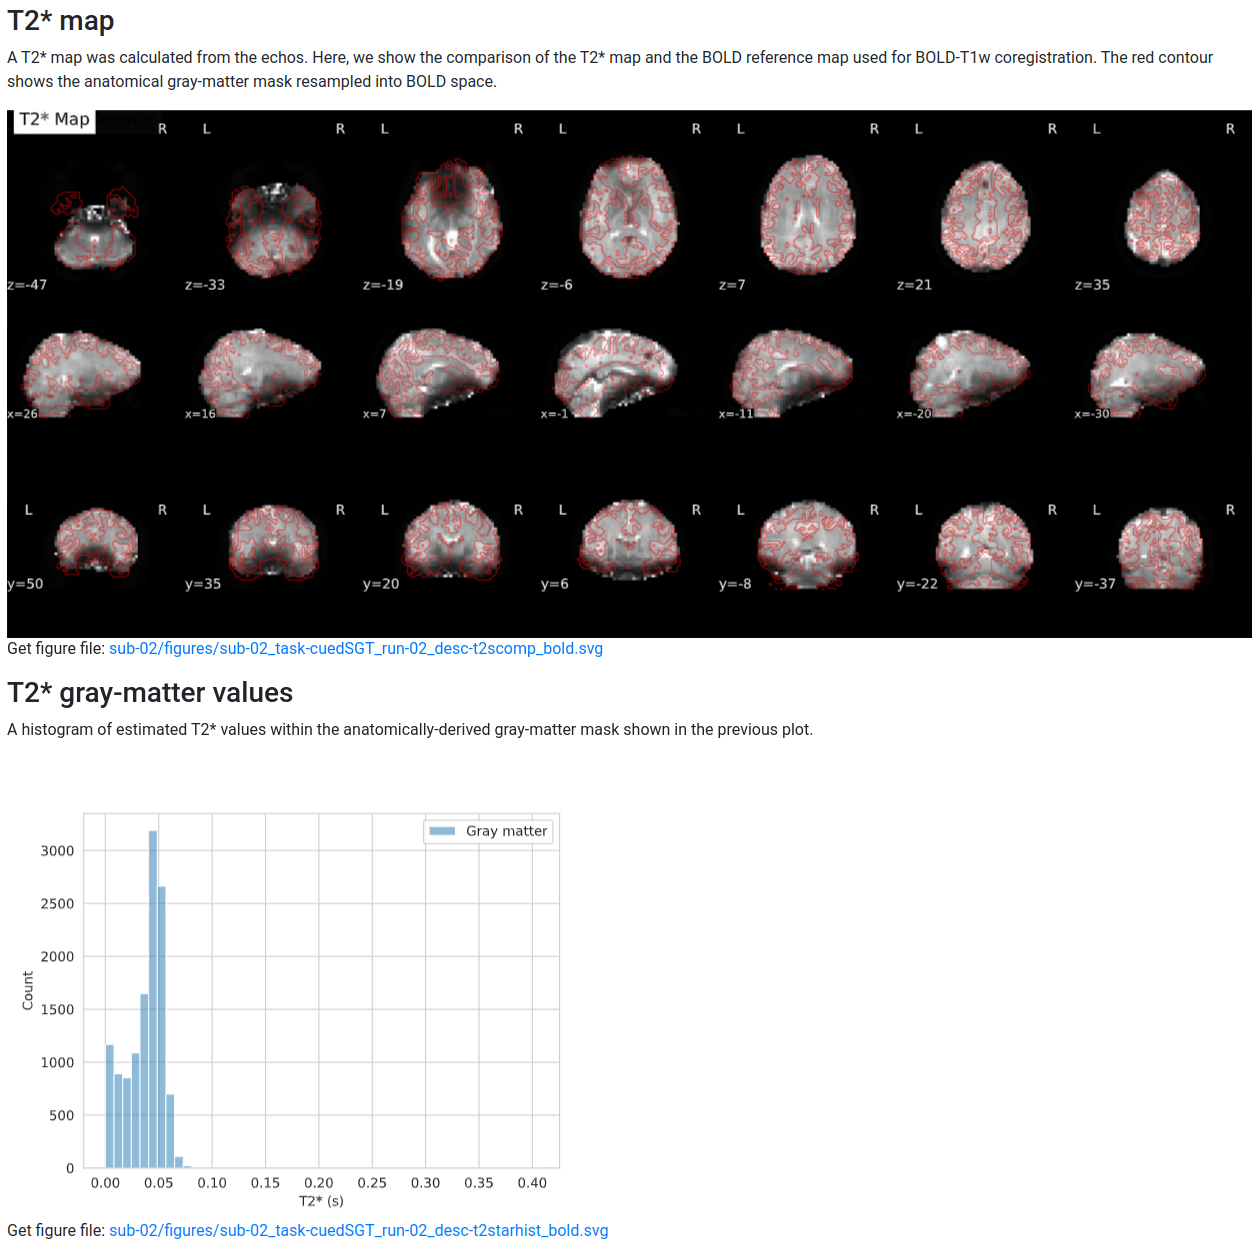

The T2* histograms are set to a certain number of bins, so a single outlier far to the right of the mode will lose a lot of specificity.

I think we should clip at a reasonably high number (100ms?) and let outliers pile up there to indicate something might have gone wrong while preserving some resolution in the modal range.

In the BOLD space there's already a lower bound at 0. I haven't made an effort to clip the resampled images in T1w/standard spaces, which do get some negative values around the edges due to ringing, as I don't think these are used for calculations.